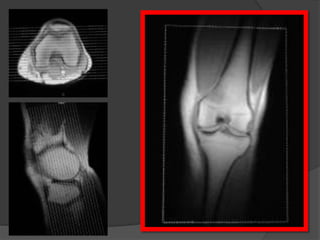

Grado 3

Grado III

• Roturas completas

• RM: solución de continuidad

completa del ligamento